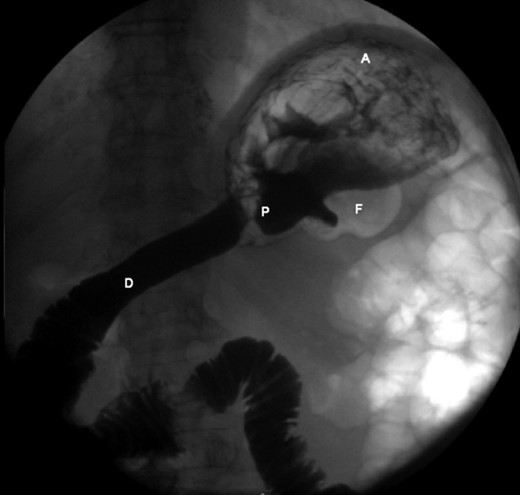

An upper endoscopy was performed, revealing a severe esophagitis with a distortion of the gastric anatomy. A great amount of stasis fluid and multiple ulcerations of the gastric fundus were present. An upper gastrointestinal series was also performed, revealing an inverted stomach, with the atrum being positioned superiorly to the fundus, with an abnormal position of the pylorus (Fig. 2).

Upper gastrointestinal series, revealing an inverted stomach, with the atrum being positioned superiorly to the fundus and a stretched duodenal arch, with an abnormal position of the pylorus.